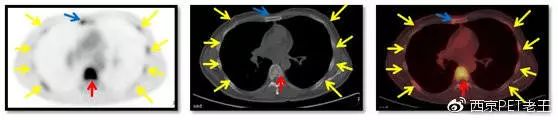

红色箭头:胸椎转移;黄色:肋骨转移;蓝色:胸骨转移

红色箭头:股骨头转移;绿色:髋臼转移;黄色:耻骨转移